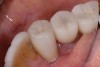

Margin location is crucial in preventing residual excess cement extrusion into the peri-implant tissues. The work of Linkevicius et al has shown that even if the margin is placed 1 mm subgingivally, cement remnants will be left behind.14 Other solutions to the problem of cement extrusion include providing custom abutments with supragingival margins 360 degrees.27 The use of etchable ceramics that are esthetically compatible with the crown, silanation, and resin bonding reduces the chance of any cement material extrusion and allows for the use of such devices as rubber dam barrier protection,28 which further reduces the possibility of cement extrusion issues (Figure 12 and Figure 13). The author is currently studying abutment modifications, with a paradigm shift: instead of considering the margin of the abutment–crown as the only site where excess cement can be expressed, the screw-access channel is being contemplated as a repository capable of retaining cement within the system itself. Simple, inexpensive modification of abutment design that involves changing the way cement flows—by internalizing the flow with internal vents (Figure 14)—also reduces the amount of cement extrusion29 and alters the retentive properties of the cemented restoration.30 With zirconia, whose subtractive material changes may weaken the structure modifications to the screw channel itself, the use of an internal insert device is also being evaluated (Figure 15). The goal, again, is to internalize excess cement and alter flow, which can change the way the system works and which is something that cannot be done with the natural tooth. Finally, using a screw-retained crown eliminates the residual cement issue completely. Screw-retained restorations have been shown to be highly esthetic and to allow for complete control of the occlusion when fabricated correctly and judiciously (Figure 16 and Figure 17).31

Figure 16

Figure 17